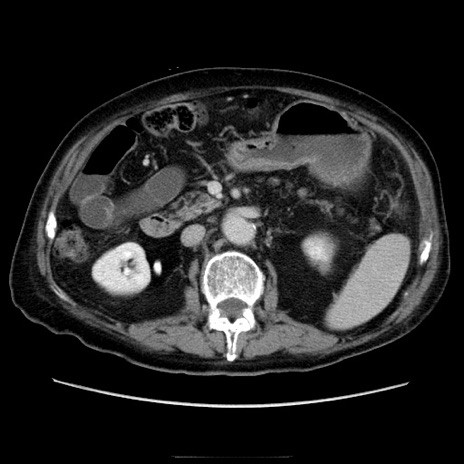

症例21(横断像)

【症例】70歳代男性

【主訴】腹痛

【現病歴】肝硬変・肝細胞癌にてかかりつけの方。約9時間前に食後より腹痛出現。症状が徐々に増悪し、嘔吐出現したため来院。

【既往歴】肝硬変、肝細胞癌(RFA、TACE後)

【身体所見】意識清明、表情苦悶様、BT 36℃、BP 129/78mmHg、P 88bpm、SpO2 97%(RA)、右上腹部から心窩部にかけて圧痛あり、反跳痛なし、筋性防御あり。

【データ】WBC 5800、CRP 0.16